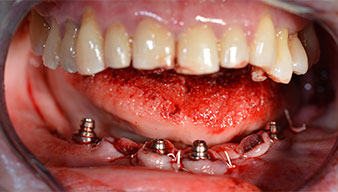

After removal of the residual dentition in the mandible, the alveolar crest was exposed from 37 to 47.

The mental foramen was first identified as a limiting anatomical structure and then the cortical bone of the crest was smoothed with the straight handpiece and a large rose-head bur (Fig. 4).

residual dentition

Fig. 4